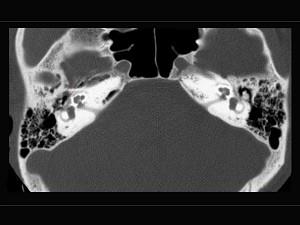

一女性患者,诉自觉听力下降,育有二子,其乳突摄片如图,可考虑为 ( )

答案: D